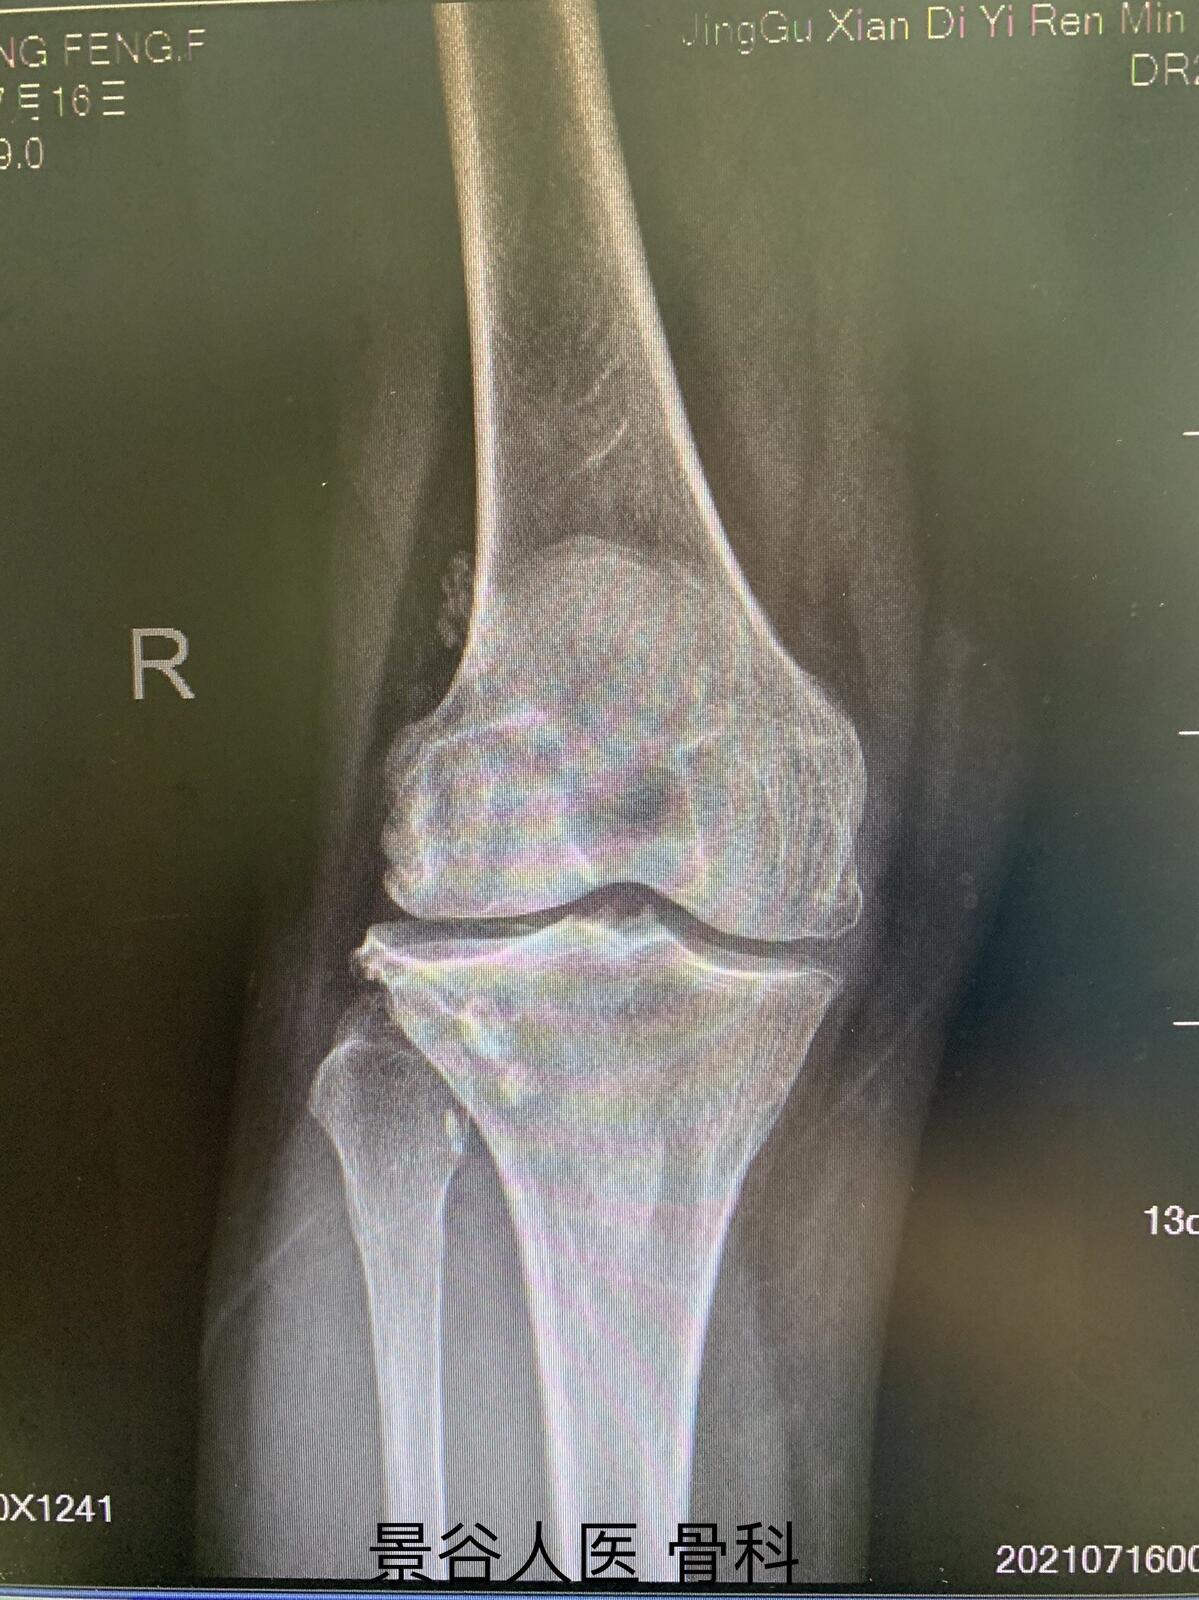

X线正侧位表现为膝关节间隙变窄,关节边缘骨赘形成、软骨下骨硬化和囊性变、髁间棘变尖、腔内多发游离体。